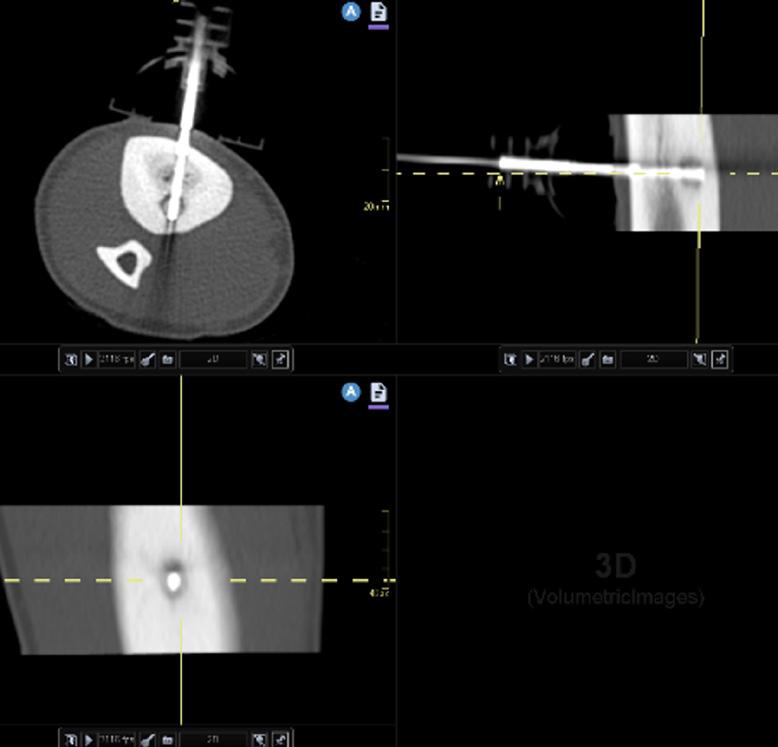

Användningen av DWI (Bild 1) skulle kunna minska behovet av kontrastmedel vid kontrollundersökningar efter tumöroperationer eftersom dagens diagnostik med konventionella MR-sekvenser till stor del bygger på bedömning av kontrastmedelsuppladdning i suspekta vävnader. DWI har dock sina begränsningar, bland annat på grund av magnetfältets inhomogenitet i ojämna områden av vår kropp (till exempel området kring axelleden där det finns en disproportion mellan dimensionerna av nacken och axlarna samt närvaron av rörliga lungor, stora kärl etc.) vilket leder till tex bildförvrängningar och artefakter. Diffusion är en känslig metod, men dess användning inom rörelseapparatens system är för närvarande inte stor, eftersom det saknas studier på större material.

Diffusion tensor imaging (DTI), (Bild 2) är en variant av DWI som syftar till att avbilda den riktningsberoende signalen hos vattenmolekylernas diffusion i vävnaden. Inom rörelseapparaten kan DTI används för att avbilda diffusionen längs muskelfibrer9 för att bedöma skador på muskler som inte är synliga i konventionella sekvenser, vilket kan vara av betydelse för att upptäcka mindre, interna muskelskador hos idrottare.10,11 I utredningen av tumörer i, eller i anslutning till, nerver kan DTI används för att bedöma huruvida diffusionen längs med nerven är påverkad och därmed ge information om nervens integritet (Bild 2). Detta är relevant i differentialdiagnosen tex mellan nervtumörer och nervskidetumörer12 eller mellan lokalt växande och infiltrativa tumörer.13,14

Bild 1. En 20-årig patient med en palpabel tumor i området kring höger höft (a - pilar). MRT visade en förändring med begränsad diffusion (b och c - streckad pil). Biopsi visade osteosarkom. a – Koronalt snitt, T2 Short Tau Inversion Recovery (STIR), b - Diffusionsviktad bild (b 800), c - Apparent diffusion coefficient.

Bild 2. En 55-årig patient med en palpabel tumör i hypothenarområdet. MRT bekräftar närvaron av en tumör i hypothenarregionen (a, b - pilar). På konventionella sekvenser (a - T1-viktad bild, b - T2-viktad bild) är differentiering mellan nervtumörer mycket svår. Diffusion tensor imaging (DTI) (c) visade att tumören inte påverkar diffusionen och att ulnarnervgrenarna ligger i tumörens periferi, vilket underlättar för kirurgen att avlägsna tumören. Radiologisk misstanke om schwannom bekräftades intraoperativt och histopatologiskt.